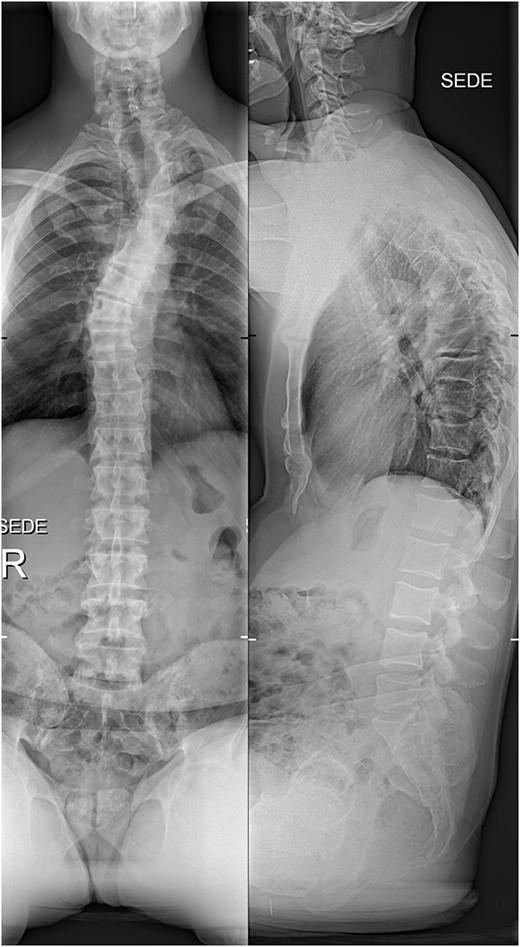

The initial X-ray images of the thoracic spine at the time of admission to our institution. Anteroposterior view (left) and lateral view (right).

The imaging studies revealed thoracic kyphoscoliosis (with a kyphotic curve of 50°, left upper-thoracic curve of 40° and right lower-thoracic curve of 25°) and significant stenosis of the thoracic part of the spinal canal (particularly at levels Th6, Th9 and Th11) due to severely ankylosed ligamentum flavum (OLF) and the concomitant degeneration of the facets (Figs 1 and 2). Imaging indicated thoracic myelopathy (Fig. 3). We performed emergent posterior wide laminectomy using an ultrasound bone scalpel, and a partial correction of the deformity by instrumented spinal fusion (Th6-Th12). The surgery was performed by the senior author (N.H.).